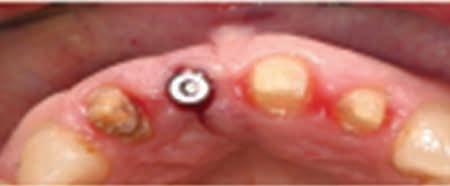

The patient returned for follow-up care in 13 days. The patient was comfortable, and in good spirits at the follow-up appointment. There were no dental or soft tissue pathologies noted at this appointment. A radiograph taken confirmed that the traumatized tooth and supporting bone did not exhibit

Figure 2. Position of the intruded tooth after surgical repositioning.

Figure 3. Radiograph of repositioned tooth with physiologic splint in place.

any pathology. Figure 4 shows the radiograph taken at this appointment. The splint was removed after confirming that the maxillary left permanent central incisor did not exhibit pathologic mobility.

The patient returned for his routine preventive visit after two months. At this visit, the traumatized tooth was free of pain or discomfort, maintained a favorable position and did not exhibit any discoloration. Thermal testing was performed and all the maxillary permanent incisors responded comparably without any lingering sensitivity. The clinical picture and radiograph at this 2-month mark is shown in Figure 5.

Figure 5. Clinical picture and radiograph at two months after intrusion injury.